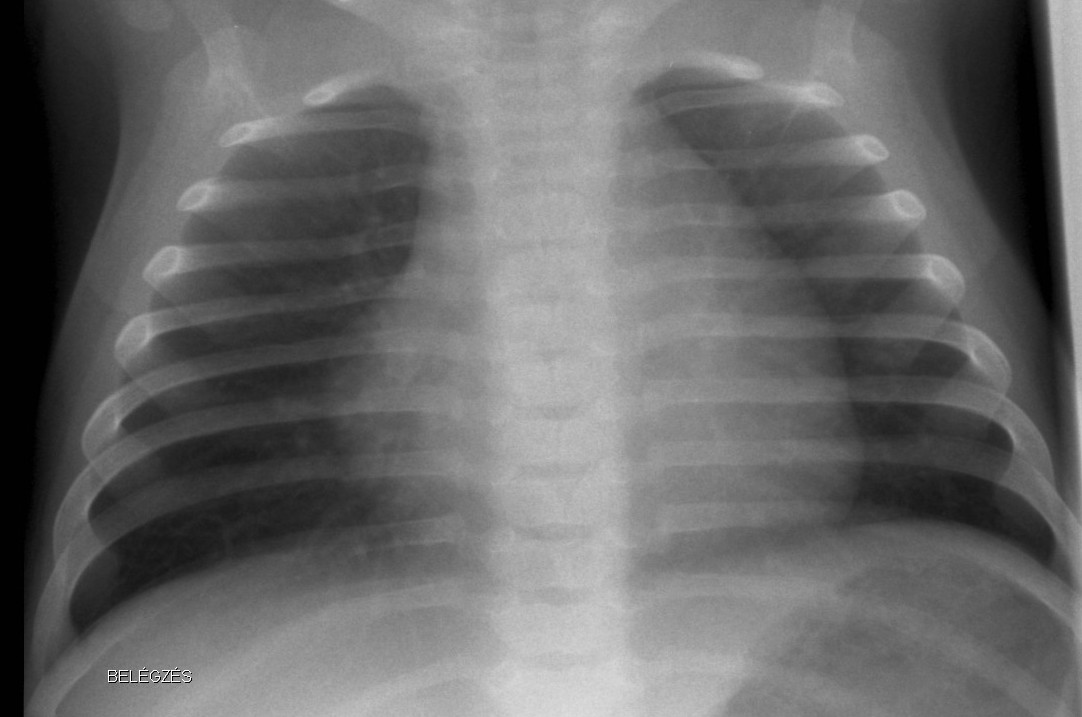

Normal newborn lungs: a newborn’s chest goes through some fundamental changes during the first days of extra-uterine life. The heart is relatively rounded, characterized by the dominance of the right side. The cardio-thoracic index taken in a mid-inspiratory state is between 0.55-0.62. Expiratory state can lead to diagnostic mistakes.

Bony thorax: the ribs are horizontal and the sagittal and horizontal diameters of the chest are very close to each other.

1.b. Inspiratory state, the lung is transparent, the heart is normal sized. Ribs run horizontally in infants.